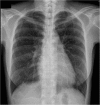

Pneumothorax in pulmonary lymphangioleiomyomatosis (LAM) with tuberous sclerosis complex (TSC) is a difficult condition to manage. Video-assisted thoracoscopic surgery (VATS) may play a role in diagnosis and treatment of this situation. We present a case of right recurrent pneumothorax due to LAM with TSC in whom VATS was performed for pathological diagnosis and mechanical pleurodesis. The unique presentation of LAM in TSC was also discussed.